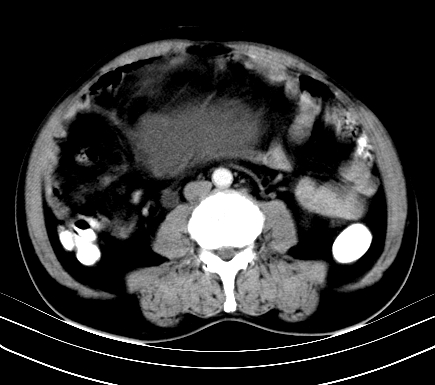

标题: CT19729B:男,74岁,因腿疼就诊,查体触腹部肿物,

增强扫描

动脉期

【ct表现】

1、肿块巨大,往往位于腹膜后,长大后才引起症状而就诊;那么位于腹膜后的肿瘤80%为恶性肿瘤。

2、实性肿瘤,增强扫描轻度不均强化,实性肿瘤一般不是好东西。

3、肿瘤边缘似见少许脂肪样密度。

4、腹膜后未见肿大淋巴结,但肿瘤于临近的肠管及组织接触紧密。

【诊断】

腹部占位,考虑位于腹膜后的恶性肿瘤,脂肪肉瘤(实体型)可能性大。

【分析】

1、腹膜后的肿瘤少见,但种类繁多,包括脂肪肉瘤、纤维组织细胞肉瘤、纤维肉瘤、平滑肌肉瘤、恶性畸胎瘤、神经肉瘤、神经母细胞瘤、血管肉瘤及横纹肌肉瘤等,其中脂肪肉瘤为较常见的一种肿瘤。

2、增强扫描强化不明显,除脂肪肉瘤以外,一般肿瘤强化中度以上。脂肪肉瘤可不强化或轻度强化。

术后病理结果:腹膜后脂肪肉瘤。